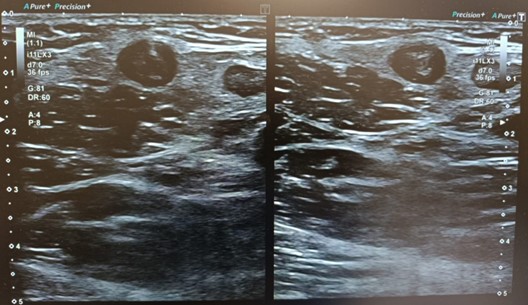

Ecografía Doppler

Ausencia de compresibilidad y material ecogénico compatible con trombosis en cayado de safena interna y externa, vena femoral superficial distal , vena poplítea y venas gemelares. Troncos tibioperoneos permeables.